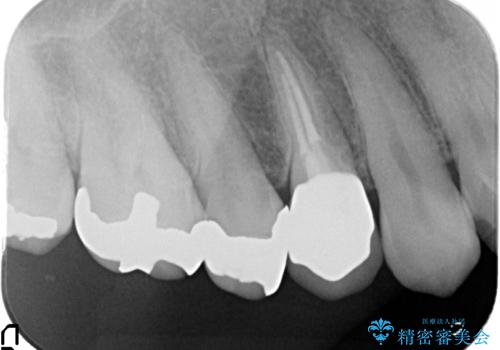

- 右上4番目の歯がなにもしなくてもズキズキ痛むといらっしゃった方の症例です。

検査の結果持続痛も認めたため、虫歯除去後根管治療を行いました。

その後オールセラミッククラウン(エクセレント)による補綴を行いました。

- オールセラミッククラウン(エクセレント)…¥180,000、仮歯…¥10,000、ファイバーコア…¥20,000費用は治療当時の料金となります